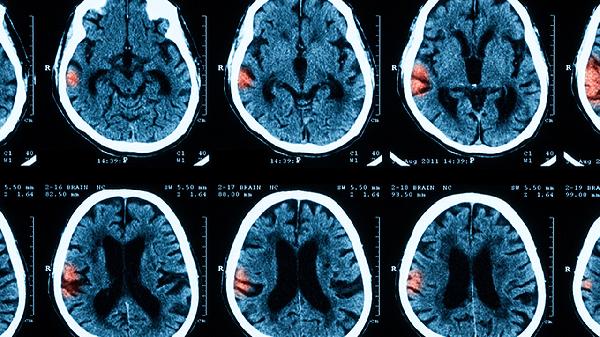

早期结核性脑膜炎的主要临床特点

早期结核性脑膜炎的主要临床特点有头痛、低热、乏力、食欲减退、脑膜刺激征等。结核性脑膜炎是由结核分枝杆菌感染脑膜引起的疾病,早期症状可能不典型,容易与其他疾病混淆。